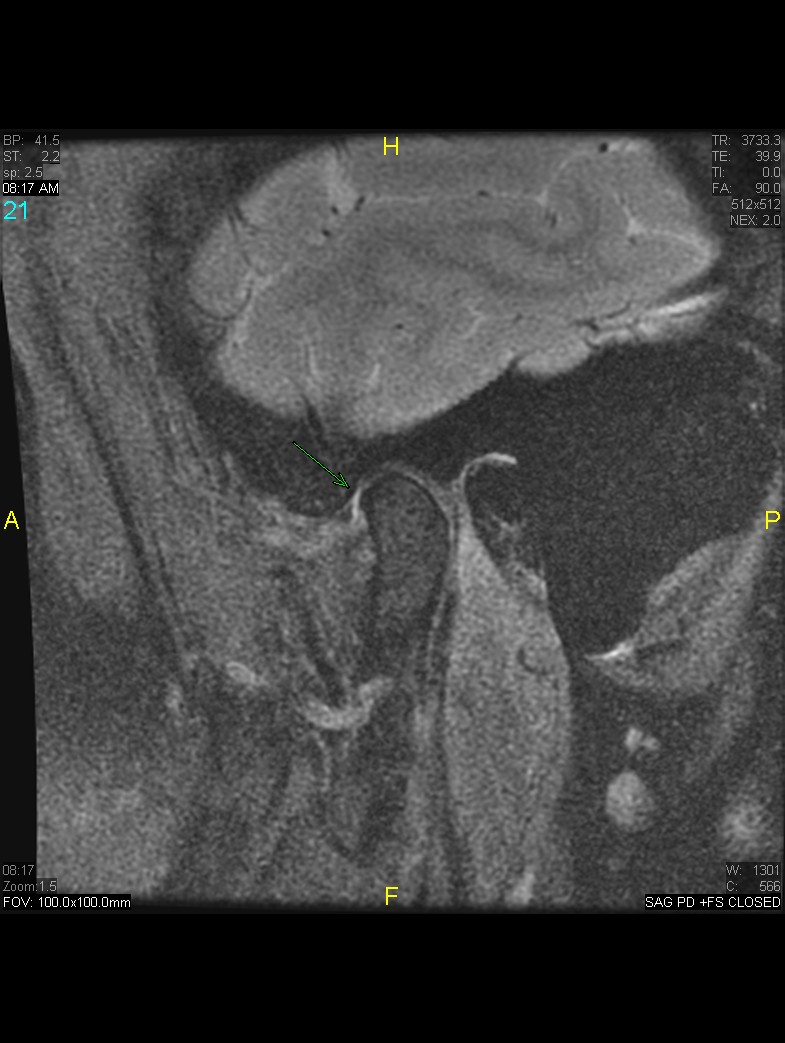

Courtesy